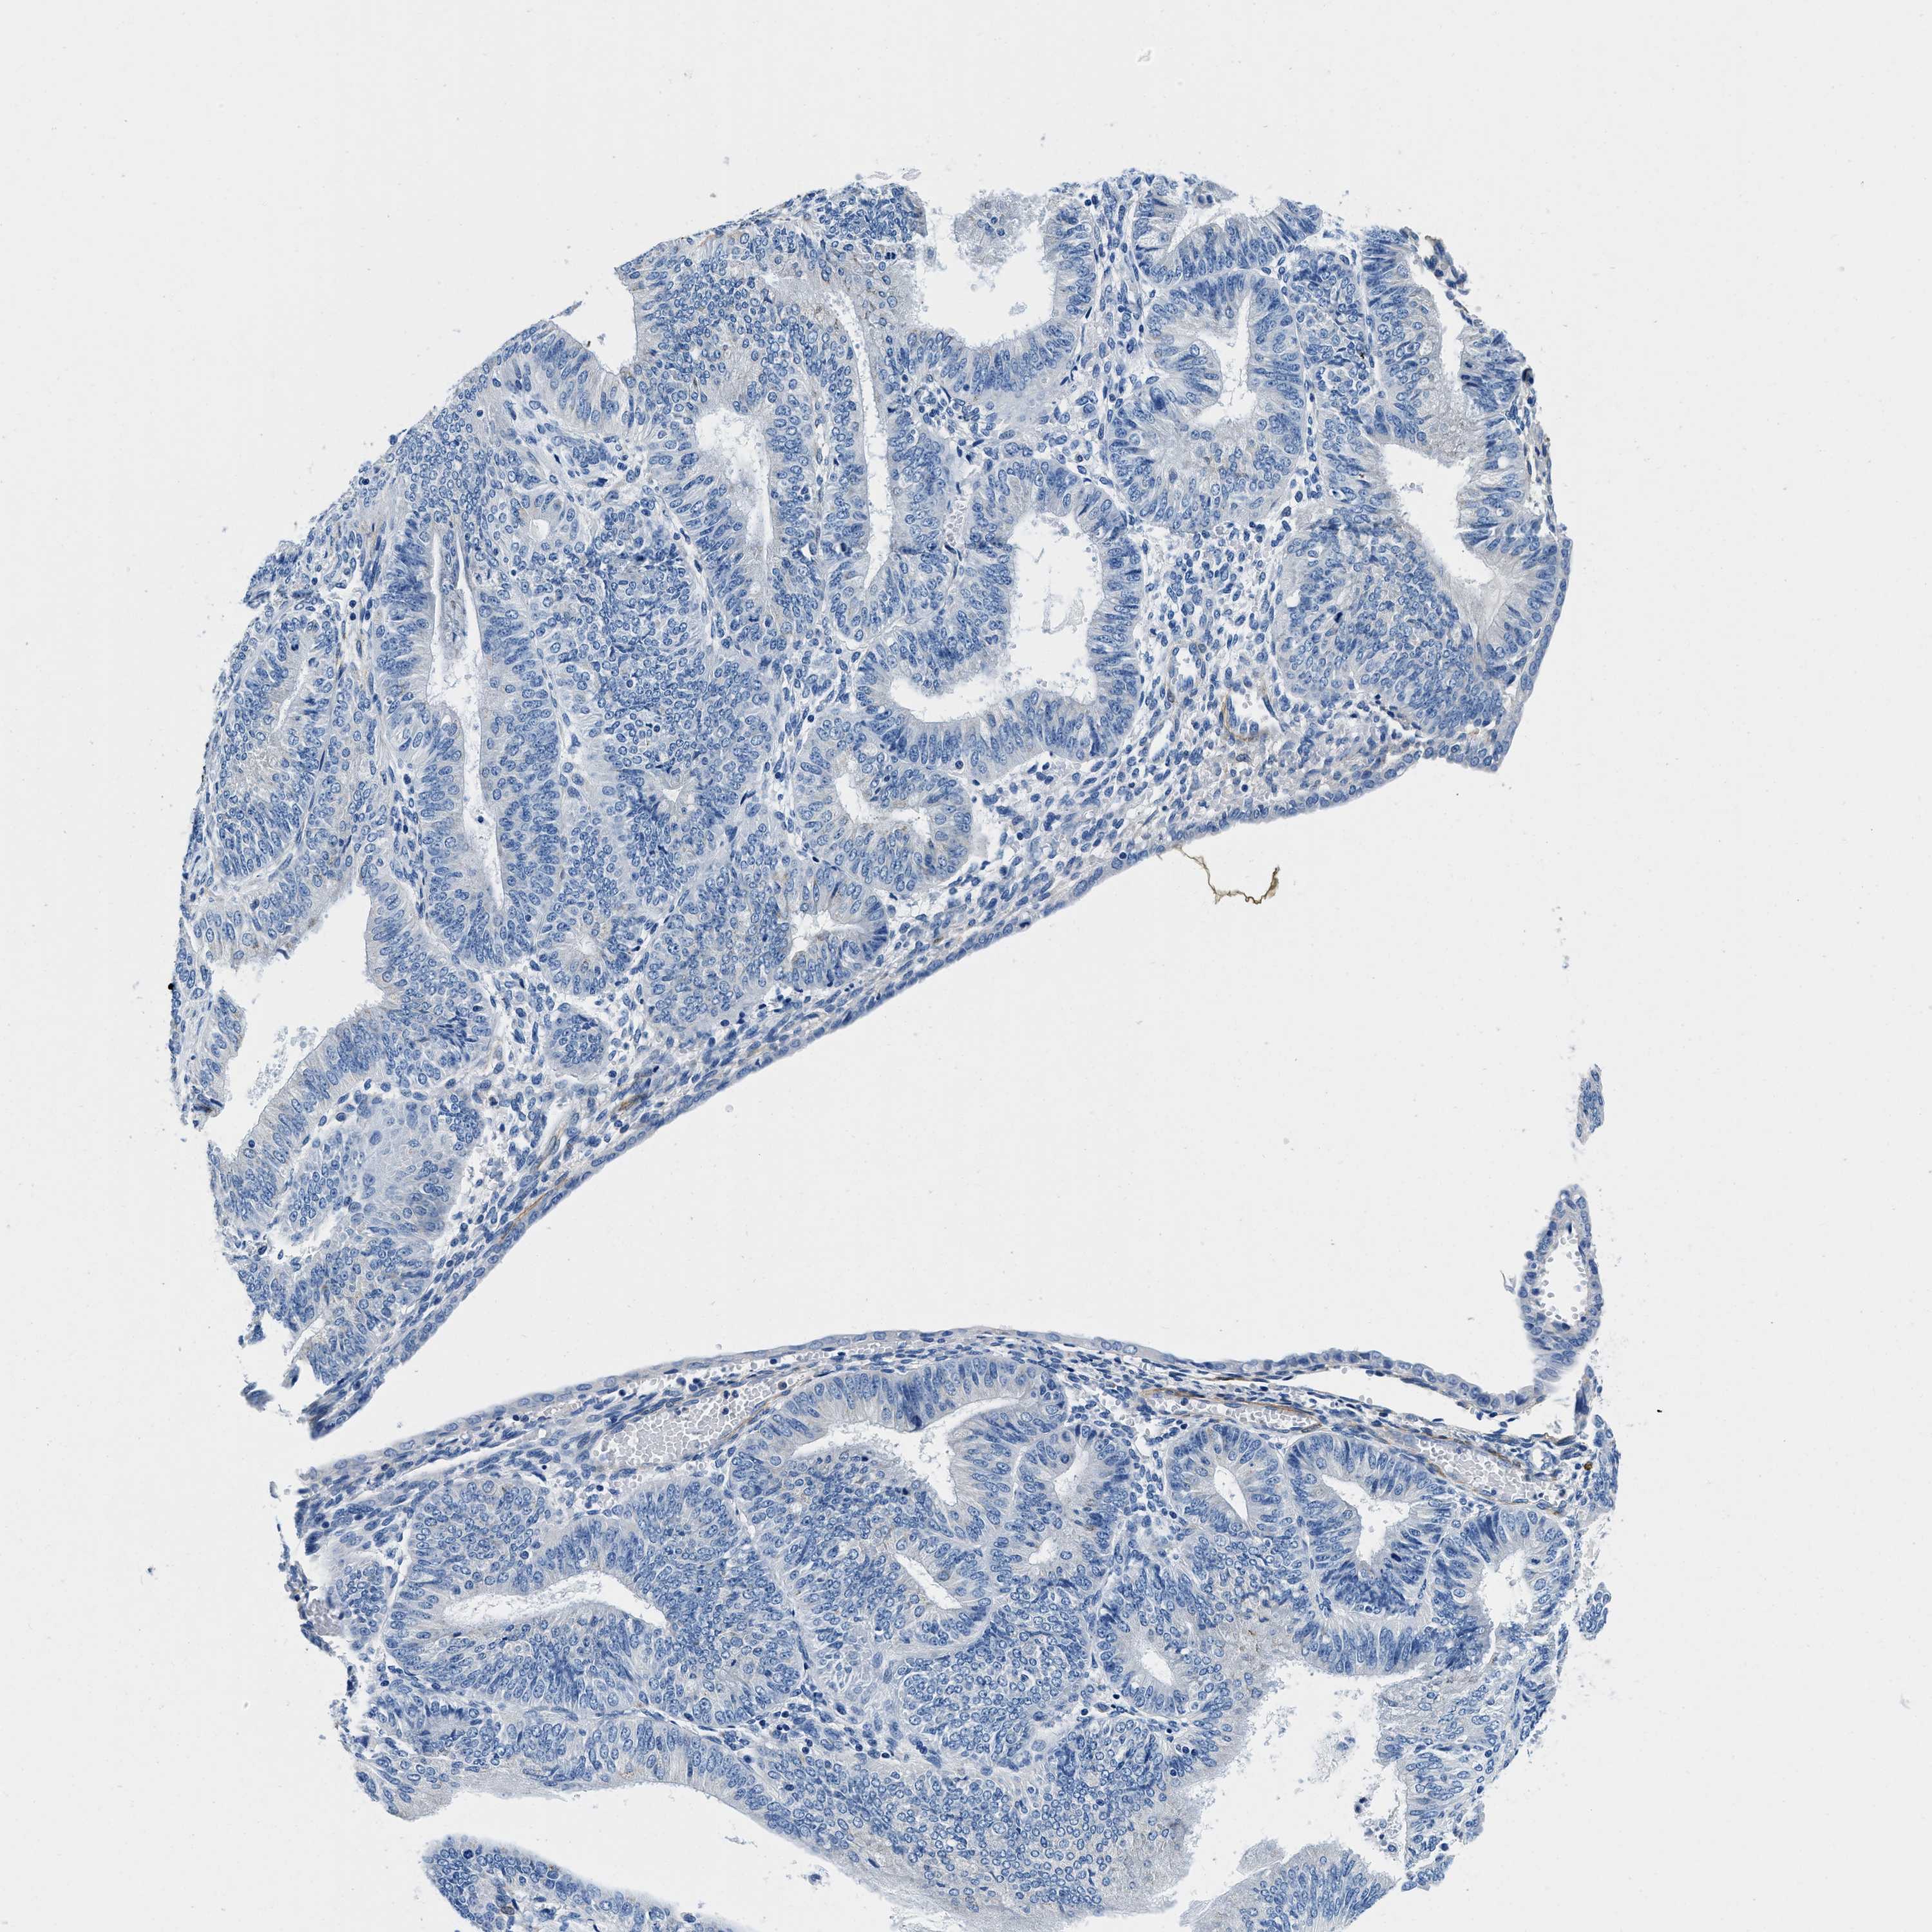

ENDOMETRIAL CANCER - Protein expressioni

A mouse-over function shows sample information and annotation data. Click on an image to view it in a full screen mode. Samples can be filtered based on level of antibody staining by selecting one or several of the following categories: high, medium, low and not detected. The assay and annotation is described here.

Note that samples used for immunohistochemistry by the Human Protein Atlas do not correspond to samples in the TCGA dataset.

Antibody stainingi

Antibody staining in the annotated cell types in the current human tissue is reported as not detected, low, medium, or high, based on conventional immunohistochemistry profiling in selected tissues. This score is based on the combination of the staining intensity and fraction of stained cells.

Each image is clickable and will lead to virtual microscopy that enables deeper exploration of all samples and also displays staining intensity scores, fraction scores and subcellular localization as well as patient and tissue information for each sample.

Antibody HPA016631

Staining

High

Medium

Low

Not detected

Intensity

Strong

Moderate

Weak

Negative

Quantity

>75%

75%-25%

<25%

None

Location

Nuclear

Cytoplasmic/membranous

Cytoplasmic/membranous,nuclear

Adenocarcinoma, NOS